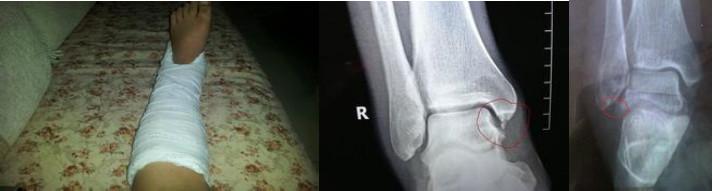

III度:损伤最为严重,疼痛和肿胀常比较明显,足底常出现明显瘀斑,外侧副韧带完全撕裂,关节出现明显不稳影响正常活动。当然如果再严重可能伴有前内踝撞击症,外踝骨折,甚至踝关节脱位等。

3级:韧带完全断裂,存在明显的肿胀和疼痛,关节不稳定。建议“U”型石膏轻度“矫枉过正”固定,康复训练同2级,但康复时间更长,少数病例需手术治疗。撕脱骨折可同法处理。